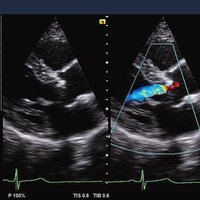

Das Siemens Acuson X300 PE ist ein mittelklassiges Herz-Kreislauf-Ultraschallgerät mit gemeinsamen Servicefunktionen. Die Premiumedition verfügt über 4D-Technologie und eine doppelte Auswahl an Sonden; zusammen mit vielen hochwertigen Funktionen ist sie in einem mittleren Preissegment erhältlich. Das Siemens ACUSON X300 PE bietet eine Vielzahl von Lösungen, einschließlich allgemeine Bildgebung, interdisziplinäre  Dienstleistungen, OB/GYN, Kardiologie, Urologie, Endokrinologie, Notfallmedizin und viele andere fachspezifische Anwendungen.

• Features: 3D, 4D, Farb/Doppler

• Kardiologie